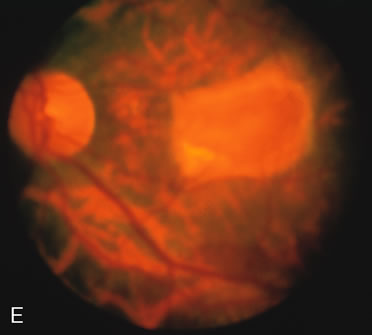

Fluorescein angiography highlights observable fundus findings. In patients with a golden reflex the FA is normal (Fig. 2E, F) or shows a mild transmission hyperfluorescence.7